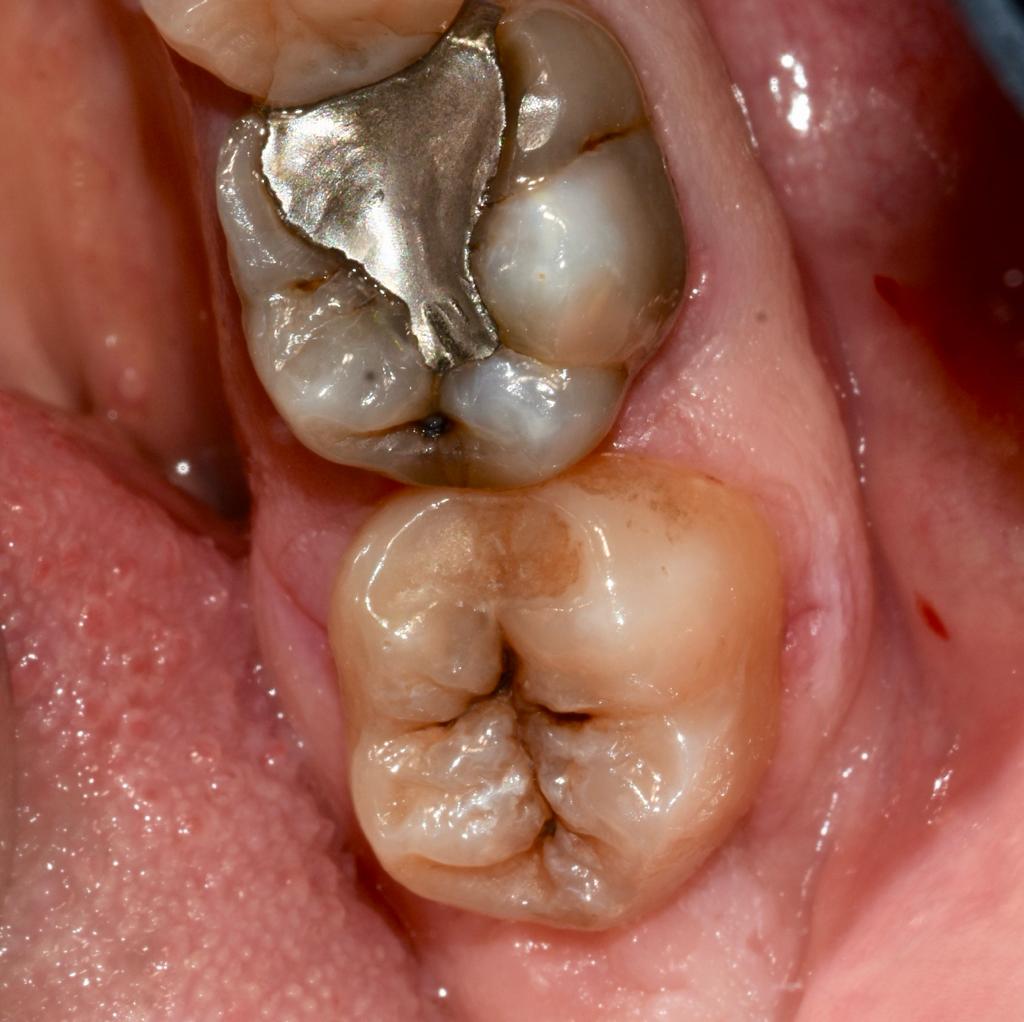

Alcuni casi clinici